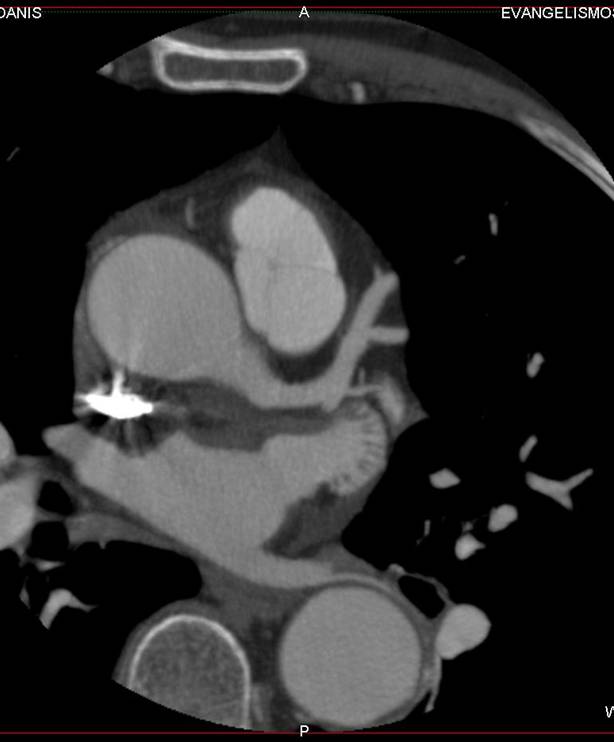

The non-invasive imaging modality of multi-detector computed tomography has dramatically evolved the last ten years and that is due to hardware and software developments. The newer generation of scanners allows increased spatial and temporal resolution that improves the clinical reliability giving further insights into the evaluation of coronary artery disease. Heart morphology imaging followed by studies of myocardial function and assessment of cardiac valves can be performed from the information derived from the data of the coronary artery examination. Also, the venous anatomy of the heart, coronary artery bypass grafts, stents, and cardiac tumors can be imaged and evaluated when necessary. For the beneficial use of this method, entrance criteria for different patient groups need to be set in order to allow improved outcome of multi-detector CT.